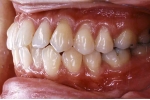

初診時